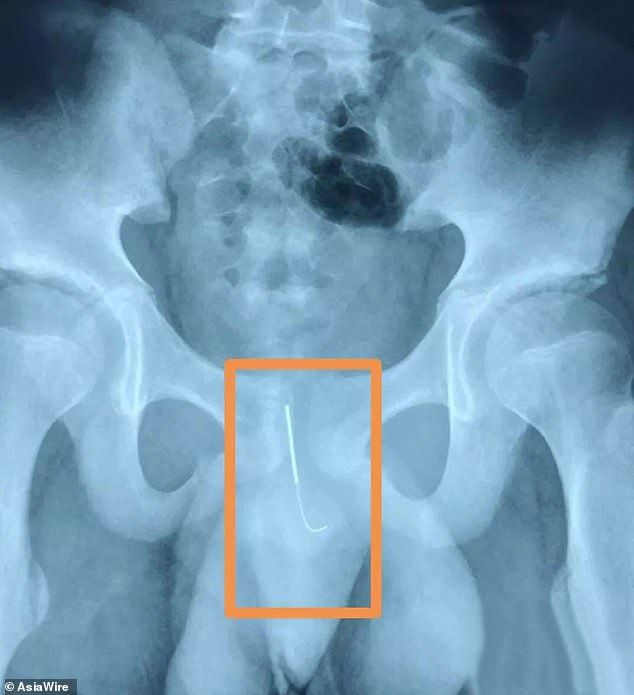

中国の12歳の男児は、4インチの鍼治療用の針を陰茎に挿入した後に緊急手術を受ける事態となった。

地元の報道によると、陝西省西安市に住む12歳の男児が金曜日の朝に病院に急行したという。母親が、彼が歩く事が困難になっている事に気がついたのだ。

シャオロンというニックネームの男児は、宿題をする為に目を覚ましたままにしようと試み、11センチの針を尿道に挿入したという。

Huashang Daily紙によると、彼はあまりにも恥ずかしかった為、両親に話すことができず、15時間後になって西安小児病院に運ばれた。

「針は尿道に深く突き刺さっており、膀胱に近い所に達していたため、排尿が困難でした。感染や出血の危険もありました。 動いたら針は彼の膀胱や動脈を破裂させる可能性がありました。」と医師は言う。